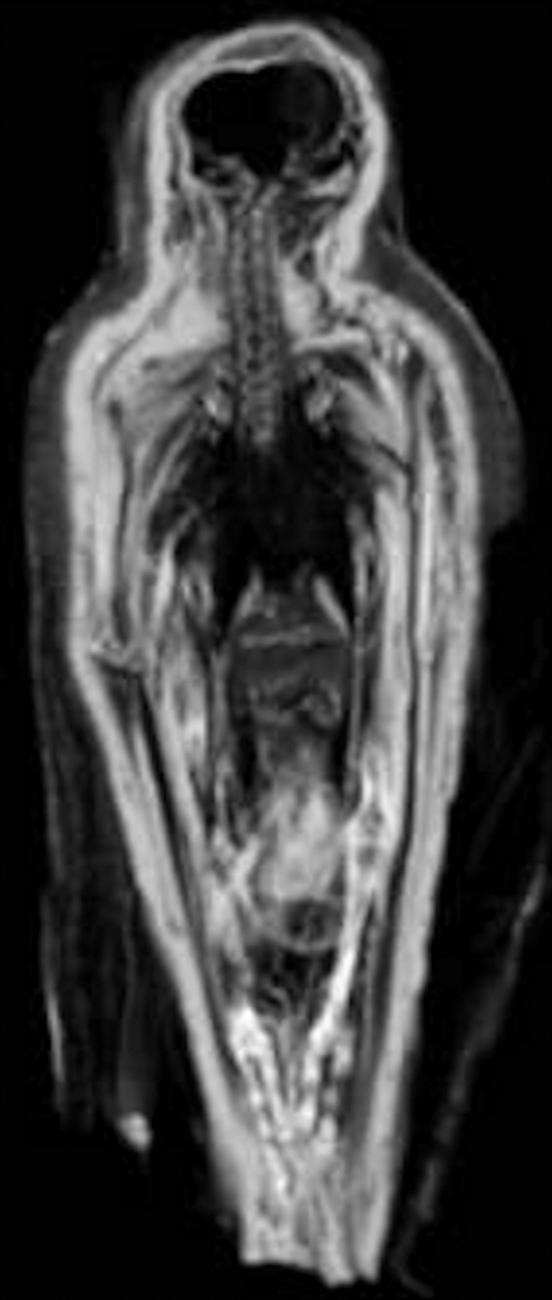

- The reduction in size of the visceral and muscle tissues; this was clearly noticeable using CT images from pre- and post-mummification (see Figure 13). It appears that desiccation is continuous, even after the anointment and wrapping methods were completed.